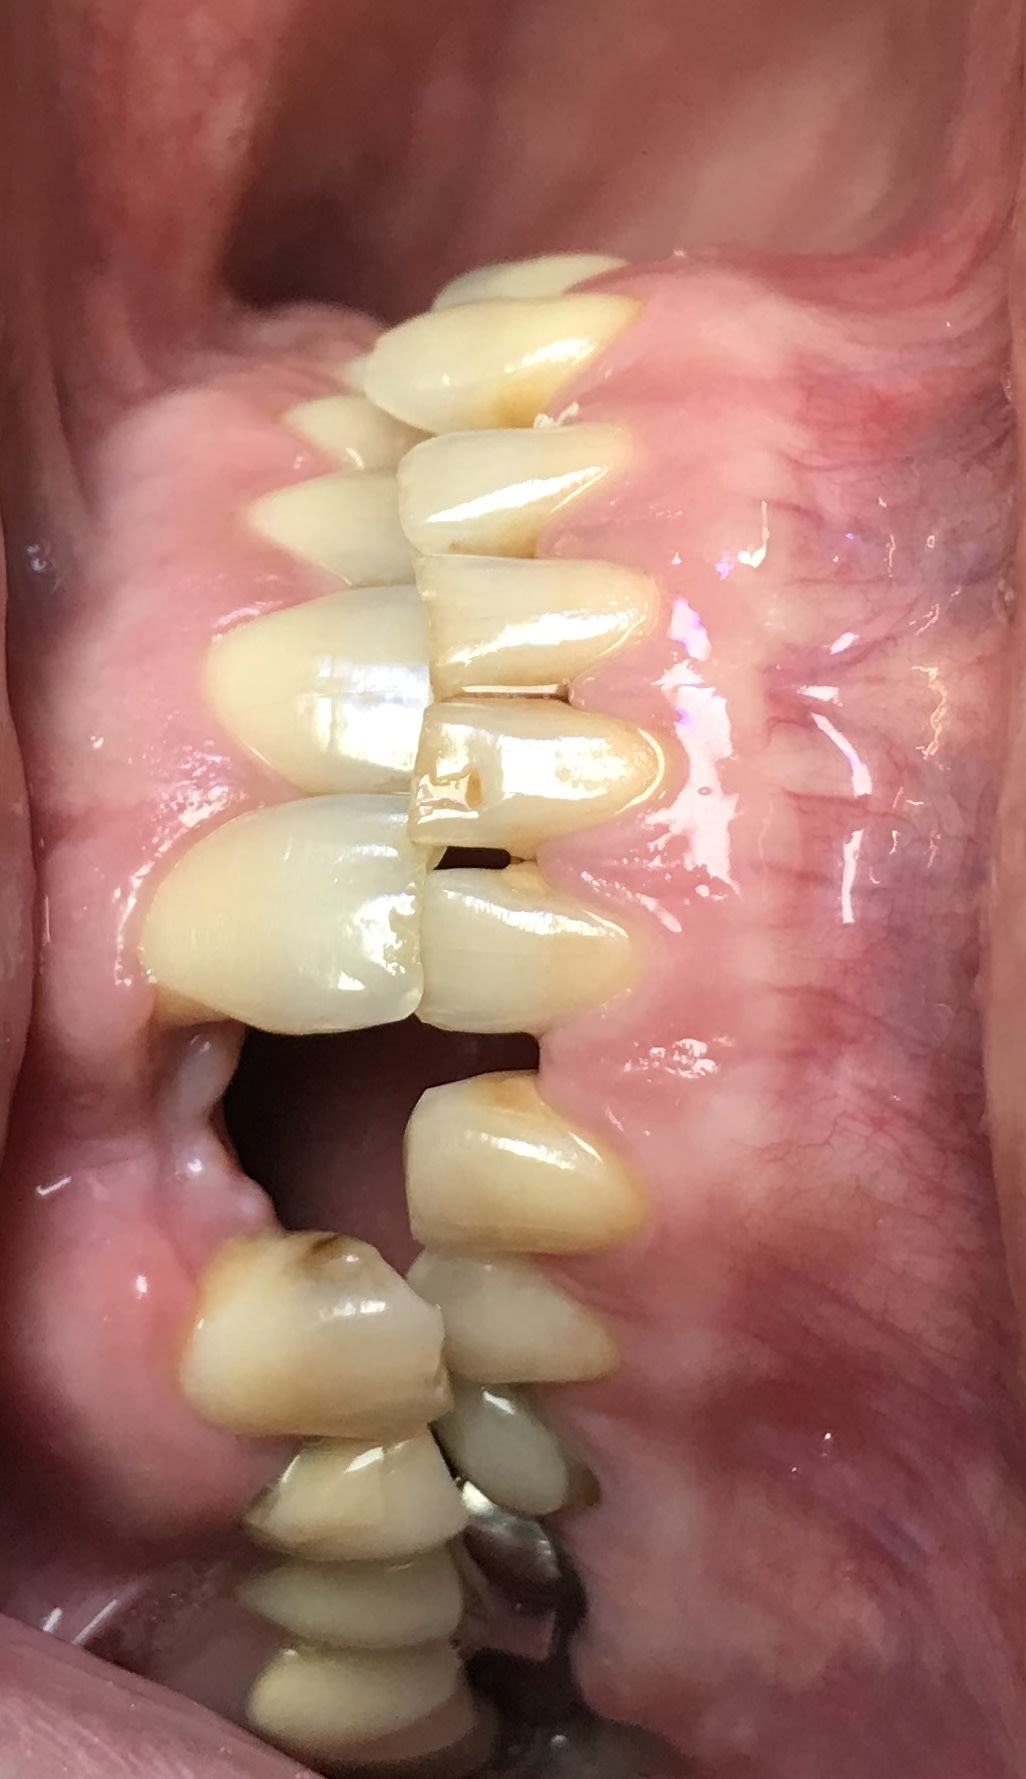

Tiens Enlaye regarde moi ça :

ça fait des années que c’est comme ça. Les courbes ne sont pas respectées. Et le patient n’a aucune douleur :) ça t’en bouche un coin, hein ?

+ la suite de mon cas « anneau dans le pif »

jolies les formes de contour de tes tailles .

tu tailles moins 1/4 de rond , et tu as vu comme la gencive est plus belle avec des limites elliptiques ?

" ça fait des années que c’est comme ça. Les courbes ne sont pas respectées. Et le patient n’a aucune douleur :) "

on a un peu l'occlusion de sa vie .

eux ils sont dans un tel caramel , qu' ils ne sauraient même pas de quelle douleur te parler .

bon mais ce n'est quand même pas une raison pour lui laisser cette molaire du haut , surtout si tu lui fais le bas , hein .